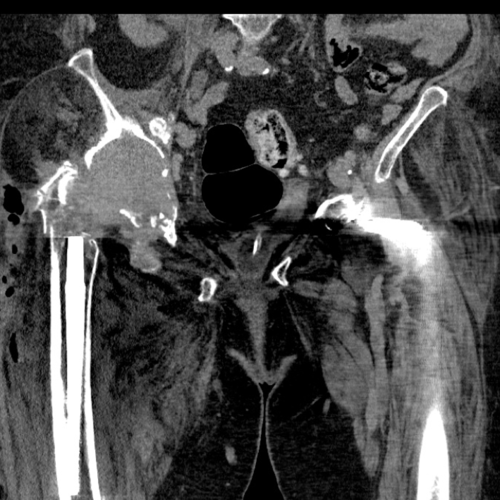

This CT scan was taken after the first stage operation to allow for the planning of a custom made trabecular titanium implant

Hemipelvic defect - This is a 3D model of the patients hemipelvis, which has been reconstructed from the CT scan shown above. This gives a better idea to both the biomechanics engineer and the surgeon about the size of the defect they are working with and allows them to design an implant to reconstruct the acetabulum.